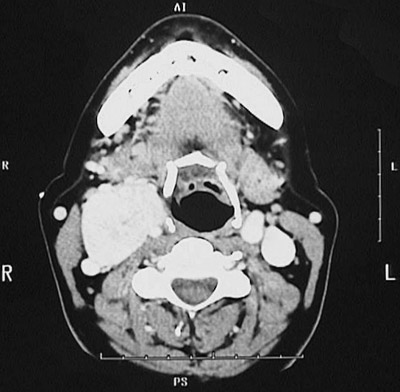

This axial head CT scan demonstrates a circumscribed mass on the right in the region of the carotid body that is consistent with a

paraganglioma

.